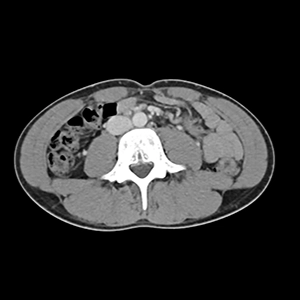

A virtual colonoscopy, also known as CT colonography, is a minimally invasive screening to check the health of your colon and rectum. This technique helps to find early signs of colon cancer or other abnormalities such as polyps, growths that can cause chronic irritation and may become cancerous over time. Instead of using a long, tube-like camera and sedation required by a traditional colonoscopy, a virtual colonoscopy uses low-dose CT technology without sedation to take high-quality images of the small intestine.

A virtual colonoscopy uses a CT scanner to take high-resolution images of your colon and rectum. These images are captured at various angles, called slices, to create a 3D view of your large intestine, similar to what your doctor would see during your traditional colonoscopy.